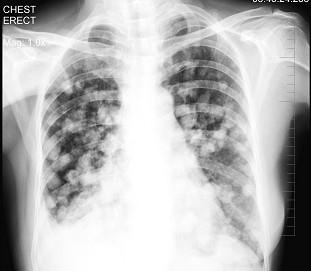

问题 女性,53岁,胸闷乏力数月,偶感胸痛,不发热,X线检查如图,最可能的诊断是 ( )

选项 A.原发性肺癌 B.亚急性血行播散型肺结核 C.肺转移瘤 D.细支气管肺泡癌 E.胸腔积液

答案 C